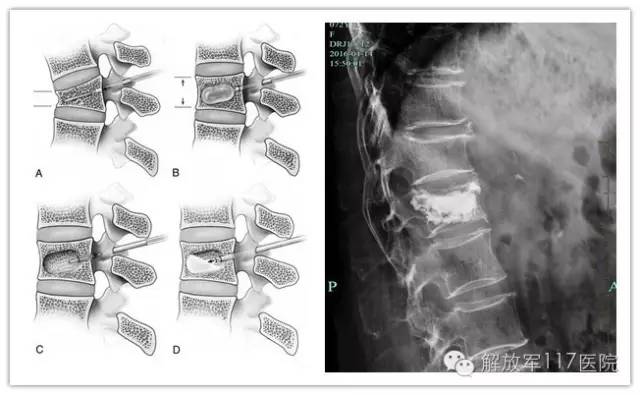

行PKP术注入骨水泥强化

目前椎体压缩性骨折的治疗方法主要有保守治疗和手术治疗两方面。保守治疗主要包括应用止痛药物、抗骨质疏松药物、卧床休息、支具固定和康复治疗等。手术治疗主要应用经皮椎体强化术 (PVA),包括经皮椎体成形术(PVP) 和经皮椎体后凸成形术(PKP),PVP 和 PKP治疗骨质疏松性椎体压缩性骨折能够实现快速止痛、恢复椎体高度、提高椎体强度与刚度、并纠正后凸畸形。

骨四科

目前开展的经皮椎体后凸成形术(PKP),是在影像导引下将穿刺针经皮穿刺到病变椎体后向椎体内注入骨水泥,以达到增强椎体强度和稳定性,防止塌陷,缓解腰背疼痛的一种微创脊柱外科脊柱技术。手术采用局部麻醉,俯卧位,耗时仅需0.5~1小时,出血小于10毫升,切口1厘米。一般术后平卧6-12小时,术后1天允许在床上坐起,第2天可佩带腰围或支具下地活动,第3天即可出院。